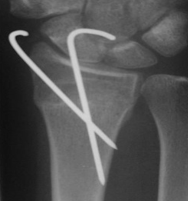

K-wire fixation